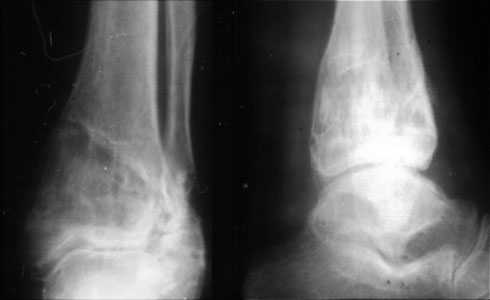

Скорее это перелом пилона 43В

Аппаратом можно сделать все минимально инвазивно и травматично, вырастить клиновидный регенерат после чрескожной остеотомии через один или два разреза 0,5 см. В приложении похожий по локализации случай, только более давние последствия травмы с замыканием части зоны роста, деформация побольше, плюс укорочение голени было.

Уважаемый Александр то что вы показали это интересно, но это два разных случая. В ваших снимках большая деформация, которая требует выращивания массивного регенерата, поэтому здесь согласен лучше аппарат, а представленном случае дефект будет небольшой поэтому накостный синтез решит все проблемы за 2 недели без ключей 8*10 в течении 3-5 месяцев.Зачем себе создавать головную боль.